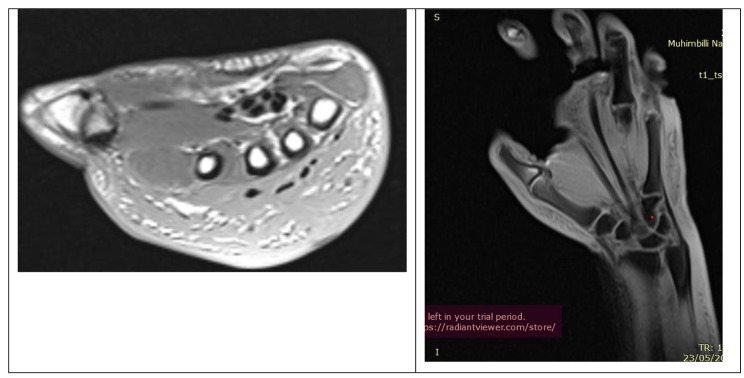

Laboratory investigations, including a complete blood count, C-reactive protein (CRP), and erythrocyte sedimentation rate (ESR), all fell within the normal range. Hand radiographs (Fig. 2) revealed significant soft tissue shadows and signs of osteopenia, without other identifiable pathologies. A CT angiogram (Fig. 3) yielded normal results, MRI (Fig. 4) showed edematous tissue in the hand and wrist. And Previously performed biopsyindicated normal tissue.

Fig. 4.

MRI images of the hand: axial and coronal cuts

CRPS can manifest differently among individuals, often requiring various imaging modalities such as MRI, CT, CT Angiography, plain radiographs, ultrasound, and other investigations to rule out alternative explanations for these presentations [12]. In our case, an MRI and biopsy were performed to exclude the possibility of a soft tissue tumor, a CT Angiography was conducted to rule out the presence of venous thrombosis, and X-rays were taken to exclude bone tumors or fractures.